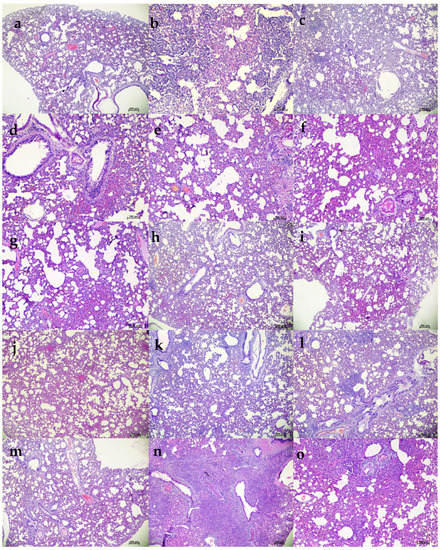

We studied the therapeutic potential with 105.5 TCID50 (high virus dose) at 24 h (Figure 6a) and 6 h post challenge and with 103.5 TCID50 (low) virus dose at 24 h after infection. In the 105.5 TCID50-challenged (at 24 h) group, no significant difference could be observed with body weight loss among groups, whereas gain in body weight was observed in the 50 mg/kg group (Figure 6b). The mAb levels in the serum remained constant from Day 3 to Day 7 without much drop (Supplementary Table S2). Although gRNA and sgRNA levels in the respiratory tract showed a decreasing trend in all the groups until 7DPI, there was no statistical significance in comparison to control in the viral load (Figure 6c–g). Grossly pneumonic changes were observed in all groups with comparable lung weights to that of placebo group. On histopathological examination, moderate to severe pneumonic changes were observed in all treated and control groups (Figure 6h, Supplementary Figure S2).

Figure 6.

mAb therapy at 24 h post high virus dose challenge in hamsters. (a) Study design, (b) percent bodyweight gain in hamsters on 3 (n = 12/group), 5 (n = 8/group), and 7 (n = 4/group) DPI. Viral genomic RNA load (n = 4/group) in (c) nasal wash, (d) nasal turbinates, and (e) lungs post infection. Viral sub genomic RNA load in hamsters’ (f) nasal turbinates and (g) lungs post infection. (h) Cumulative score of lung pathological changes in hamsters (n = 3/group) post virus challenge. Mean ± SD is plotted on the graph, and a comparison was performed between the treated groups and the control groups. A Kruskal–Wallis test followed by Mann–Whitney test was used to assess statistical significance. An asterisk indicates a significant difference between the means, with * representing p < 0.05, respectively, and the dotted line on the graph indicates the assay limit of detection.

Further, we performed therapeutic evaluation of the mAb cocktail (50 and 5 mg/kg) at 6 h post virus (105.5 TCID50) infection to understand the ability of mAb to neutralize at a shorter interval treatment (Figure 7a). The body weight reduction was observed in both the treated groups (Figure 7b). Although the placebo group showed considerably higher body weight loss than the mAb-treated groups, it was not statistically significant. The average gRNA load in nasal wash, nasal turbinate, and lungs on 3 and 5 DPI did not show any significant difference among groups (Figure 7c–e). SgRNA levels showed reduction in comparison to the placebo group and were completely cleared from nasal turbinates and lungs by 5 DPI in all mAb-treated groups (Figure 7f,g). On histopathological examination, mild changes were seen in the 50 mg/kg dose group, whereas the hamsters of the 5 mg/kg group showed to mild to moderate changes, and the placebo group showed moderate pneumonic changes (Figure 7h, Supplementary Figure S3).

Figure 7.

mAb therapy at 6 h following high virus dose challenge in hamsters. (a) Study design, (b) percent bodyweight gain/loss in hamsters on 3 (n = 6/group) and 5 (n = 3/group) post SARS-CoV-2 infection. Viral gRNA load (n = 3/group) in (c) nasal wash, (d) nasal turbinates, and (e) lungs in hamsters post virus challenge. Viral sgRNA load (n = 3/group) in (f) nasal turbinates and (g) lungs in hamsters post virus challenge. (h) Cumulative histopathological score of lung pathological changes in hamsters (n = 3/group) on 3 and 5 DPI. Mean ± SD is plotted on the graph, and a comparison was performed between the treated groups and the control groups. A Kruskal–Wallis test followed by a Mann–Whitney test was used to assess statistical significance. The dotted line on the graph indicates the assay detection limit.